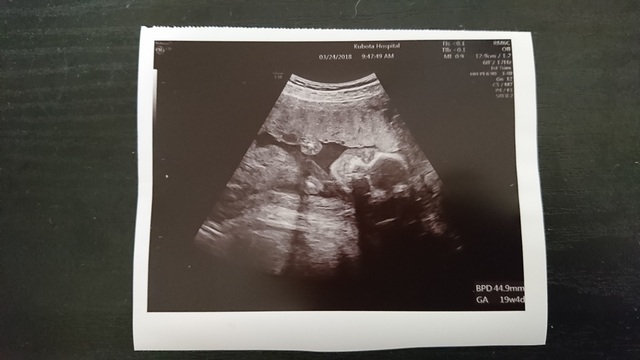

19週1日(19w1d・性別不明)|ゅんゅん さん(30歳)

エコー写真撮影時のエピソード:

横顔です!鼻も高そうだし、唇も可愛いです。今1歳10ヶ月の娘の時は、エコーでも鼻が低かったので低いまま産まれました(笑)

ちゃんとお姉ちゃんになれるか心配です。「赤ちゃんどこ?」と聞くと、必ず自分のお腹をさすり「ここ!ここ!」と言ってます。(笑)

でも、私が「赤ちゃんにチューして」と言えば、私のお腹にチューしてくれます。わかってるのか、わざとしているのか…